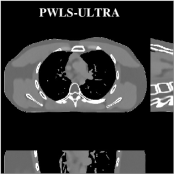

Fig.Β 7 shows the reconstructions (shown for the central axial plane in the 3D volume) for FDK (provided by GE Healthcare), PWLS-EP (corresponds to Fig.Β 8(a)), and PWLS-ULTRA with (corresponds to Fig.Β 9(a)). The PWLS-ULTRA reconstruction has lower artifacts and noise. Moreover, the image features and edges are better reconstructed by PWLS-ULTRA than by PWLS-EP or FDK.

Fig.Β 8 shows the reconstructions (shown for the central axial, sagittal, and coronal planes in the 3D volume) for PWLS-EP with different regularization strengths , denoted as a multiplicative factor of the parameter value in Fig.Β 7. Fig.Β 9 shows the reconstructions for PWLS-ULTRA (with patch-based weights) with different parameter combinations. For the sagittal and coronal planes, we show the central out of axial slices. Larger regularization strengths would achieve more noise reduction but simultaneously lower spatial resolution in PWLS-EP and PWLS-ULTRA, e.g., compare Fig.Β 8 and Figs.Β 9(a) and (d). Larger values of would achieve lower sparsities and more noise reduction but potentially oversmooth the image, e.g., compare Figs.Β 9(c) and (d). Small values of may introduce additional spurious noise in the PWLS-ULTRA reconstruction (compare Figs.Β 9(a) and (b)). Fig.Β 11 shows profiles of chest reconstructions (plotted from the central axial slice) for the PWLS-EP and PWLS-ULTRA methods. The profile locations are shown in green lines in Fig.Β 7. Both PWLS-EP with regularization strength X and PWLS-ULTRA (with patch-based weights) in Fig.Β 9(a) have lower noise than the PWLS-EP with regularization strength X. Though the spatial resolution of PWLS-EP with regularization strength X is close to PWLS-ULTRA in the selected soft-tissue regions, PWLS-ULTRA reconstructs bone and spine areas with higher resolution, and preserves small features better (compare the zoomed-in areas in Fig.Β 8 and Fig.Β 9).